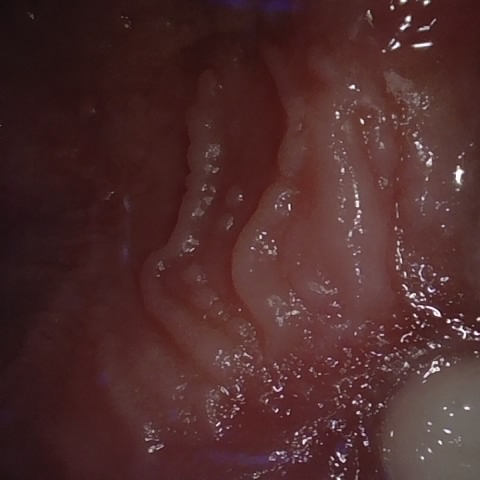

NHD39174

Annotated as "Good"

Original Image Rendering Image